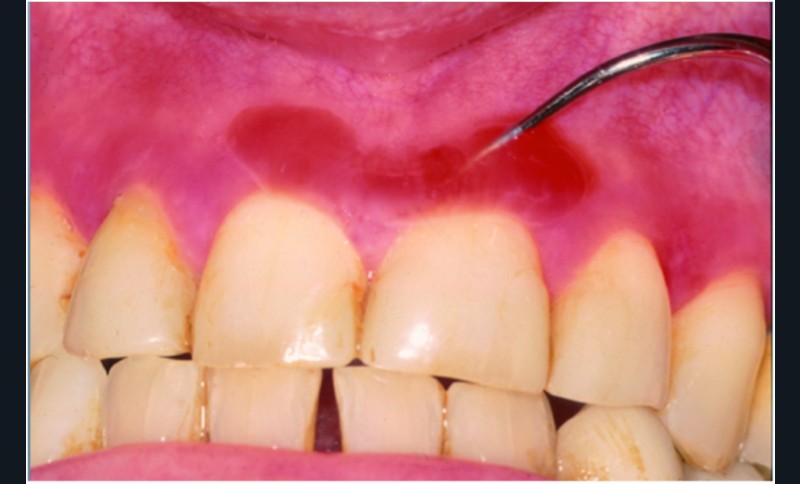

Il existait un érythème diffus mais irrégulier, intéressant la fibro-muqueuse gingivale vestibulaire, surtout supérieure. L’érythème, peu marqué, n’était pas limité au bord libre de la gencive et pouvait toucher la fibro-muqueuse sur toute sa hauteur. Dans la région médiane supérieure, on observait une large bulle avec un contenu hémorragique.

La biopsie et l’examen en immunofluorescence directe ont confirmé le diagnostic de pemphigoïde cicatricielle des muqueuses.

Synthèse. La pemphigoïde cicatricielle des muqueuses est une maladie bulleuse auto-immune qui touche principalement la fibro-muqueuse gingivale, surtout chez des femmes âgées. Elle est souvent initialement considérée comme une banale gingivite. En phase d’activité, on peut observer un dépôt blanchâtre au collet des dents correspondant à un exsudat fibrineux. Comme ce dépôt se forme rapidement et qu’il ressemble à de la plaque, les patients sont régulièrement accusés d’être responsables de leur gingivite en raison d’une hygiène bucco-dentaire insuffisante. L’examen microscopique montre un décollement sous-épithélial avec un dépôt linéaire d’IgG et de C3 sur la membrane basale. Il existe une dizaine d’antigènes-cibles, mais le plus fréquent est le BPAg2 de 180 kD. Il faut systématiquement…